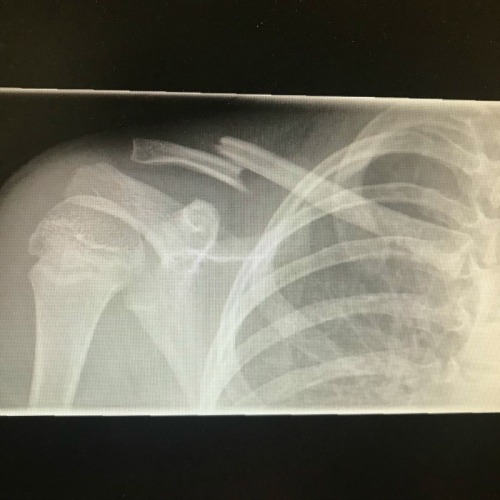

“Just 3 days after I make the gymnastics team I fall and break my clavicle,” Fernandez said. “Found out today I don’t need surgery! Need ideas for low key things to do while my friends are at the pool!” Since Fernandez didn’t end up on the operating table, that’s certainly a bright spot in all this. She’s also looking for interesting hobbies to try out, so she’s obviously making the best of a bad situation.

Fernandez revealed more details about her recovery process on Instagram. It’ll definitely take a while to get back to normal. Fernandez admitted, “It has been very painful, and I can’t do ANYTHING active for at least two months…” That’s a bummer, but GH viewers are sending her lots of love and sympathy. We’re all rooting for Fernandez to hang in there and have some fun this summer anyway.

Just 3 days after I make the gymnastics team I fall and break my clavicle. Found out today I don’t need surgery! Need ideas for low key things to do while my friends are at the pool! #minifern #scarlettischarlotte #childrenshospital #generalhospital #gh pic.twitter.com/qNp3A46QoT